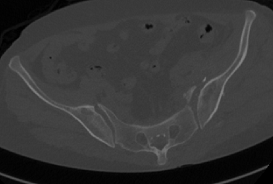

术前CT和术后CT比较

整个手术1小时内完成,通过术后CT影像证实3D打印导航模板引导骶髂螺钉置入安全、准确、创伤较小,手术时间短,患者也很快得到了较好的恢复。